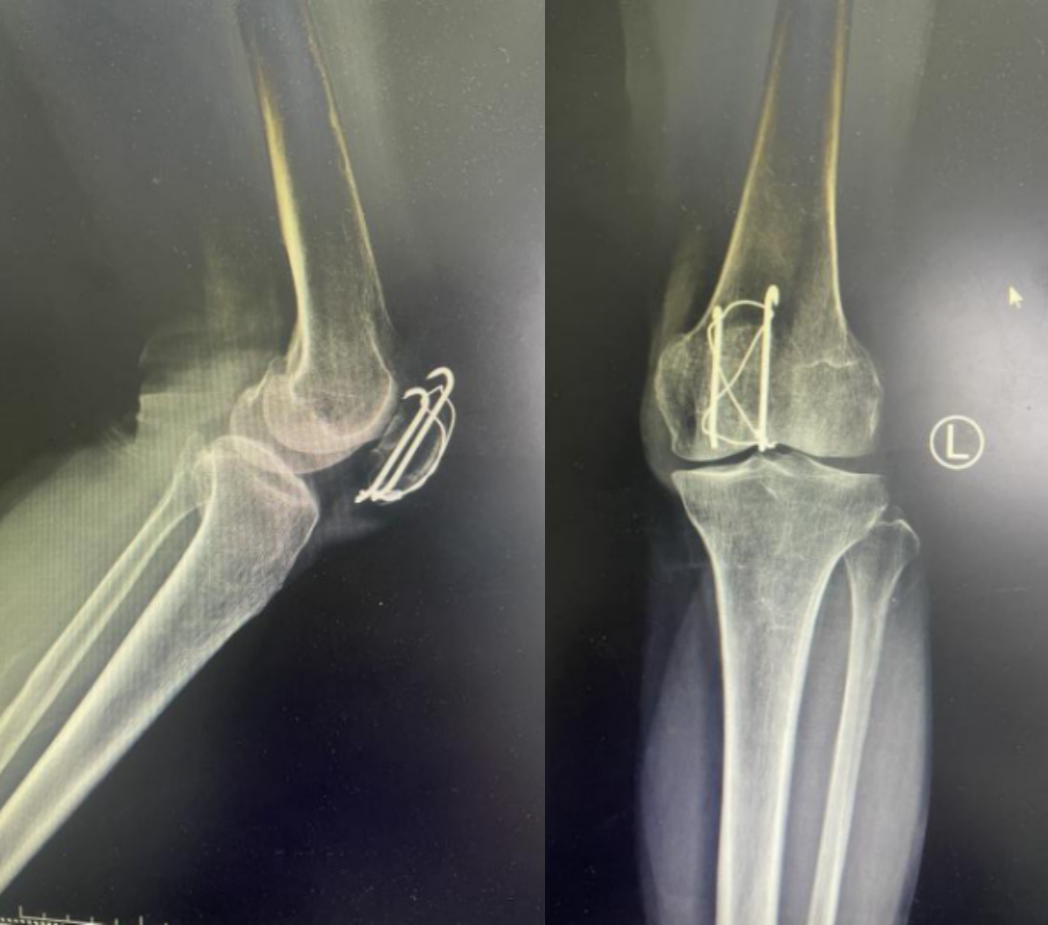

髌骨骨折只占全身骨折的 1%,治疗方式的选择和并发症的防治尤其要注意,急诊来了髌骨骨折患者,你怎么处理?髌骨是人体最大的籽骨,位于膝关节伸膝装置内。解剖特点包括近端宽大的基底和关节外的远侧尖端,前面位于关节外,后面为关节面。股直肌和股中间肌止于髌骨基底部,股内侧肌和股外侧肌止于髌骨的两侧。髌腱起于髌骨尖端,止于胫骨结节。髌骨骨折约占所有骨折的 1%,主要由直接暴力造成,如跌倒时跪地或膝关节屈曲时受到打击。典型的体征包括关节肿胀、压痛、伸膝功能部分或完全丧失。除以主诉和典型体征外,膝关节 X 线片也是必不可少的一项辅助检查,以膝关节正侧位 X 线片最常见,如果怀疑纵向骨折,膝关节屈曲 45° 时髌骨 30° 切位片可以辅助诊断。对于骨折不愈合、畸形愈合所致的关节面不平整以及髌股关节对应关系不良可采用 CT 检查。MRI 有助于诊断软骨缺损和损伤。34-B 型(部分关节内骨折,伸膝装置完整,如纵行骨折)髌骨下极骨折袢钢板结合克氏针、张力带固定 图源:作者提供

拉力螺钉加张力带钢丝固定或经胫骨结节绕髌环扎;经骨缝合撕裂的肌腱加髌骨和胫骨结节间钢丝环绕以加固缝合;袢钢板固定。无移位采用非手术治疗;移位并且单纯骨折采用横向拉力螺钉固定,骨质疏松患者需加环扎固定;对于多骨折块(星状)则采用髌骨环扎加张力带进行固定。克氏针加张力带钢丝;有第三个骨折块则采用拉力螺钉或克氏针加张力带钢丝固定;对于 4 个或 4 个以上的骨折块采用克氏针加螺钉加张力带钢丝进行固定;对于严重粉碎和软骨面广泛破坏的髌骨骨折,髌骨部分或完全切除也是一种可行的办法。

术中切开显露髌骨时,最理想的的分离层面为皮下筋膜和伸膝装置之间,如若在皮肤和皮下筋膜之间进行分离,可能会造成伤口边缘坏死。对于开放性髌骨骨折应及时给予清创处理,对于闭合性髌骨术后感染患者应及时进行清创灌洗直至伤口愈合。如有深部感染则推荐长期使用抗生素。透明降解物会产生轻重不等的无菌性滑膜炎,这很难和感染相区分。需行关节镜检查来确定。在进行克氏针固定髌骨时,克氏针的末端应剪短,否则有穿破皮肤以及术后活动时疼痛的风险。髌骨骨折术后内植物至少在损伤后 9 ~ 12 个月才能取出。高密度的骨皮质需要这么长时间才能愈合,从而能在无保护情况下承受高张力。必须防止这一并发症的发生,因为会导致膝关节屈曲严重受限。用环扎钢丝来保护髌腱时,有可能因为错误估计髌腱长度而造成髌骨低位。髌骨的正常位置可以参照健侧膝关节的 X 线片。屈曲受限的患者需要进行强化理疗。如果在数月内运动的范围没有增加,下一步可行关节镜下松解,去除髌上囊的挛缩瘢痕。如果髌骨已切除,则可能出现肌腱断裂的晚期并发症。髌骨软骨面的严重损伤、关节面不平整的继发性损伤以及髌股关节受力的改变,都将导致创伤性关节炎的发生。如果髌骨韧带附着位置太靠前方,会使髌骨下极位置靠后,也将导致创伤性关节炎。在前一种情况下,可以行关节镜下清理;后一种情况下需改变韧带附着点位置。髌骨术后应及时有效地进行膝关节活动锻炼,一般在术后 3 月时膝关节可屈曲 120° 以上,若术后 3 月时膝关节弯曲角度仍然小于 90°,建议进行辅助康复训练,必要时以手术松解。